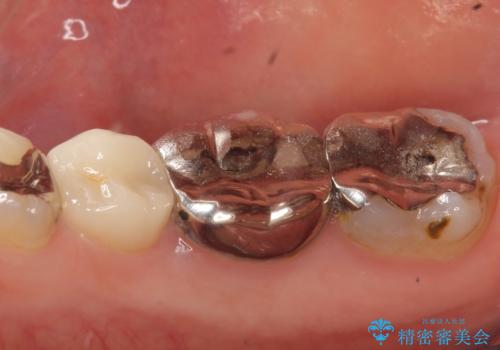

- 右下奥の歯茎がたまに腫れて膿が出るので診て欲しいといらっしゃった方の症例です。

診査の結果右下6の歯の神経が死んでいたため根管治療を行い、オールセラミッククラウンによる補綴を行いました。